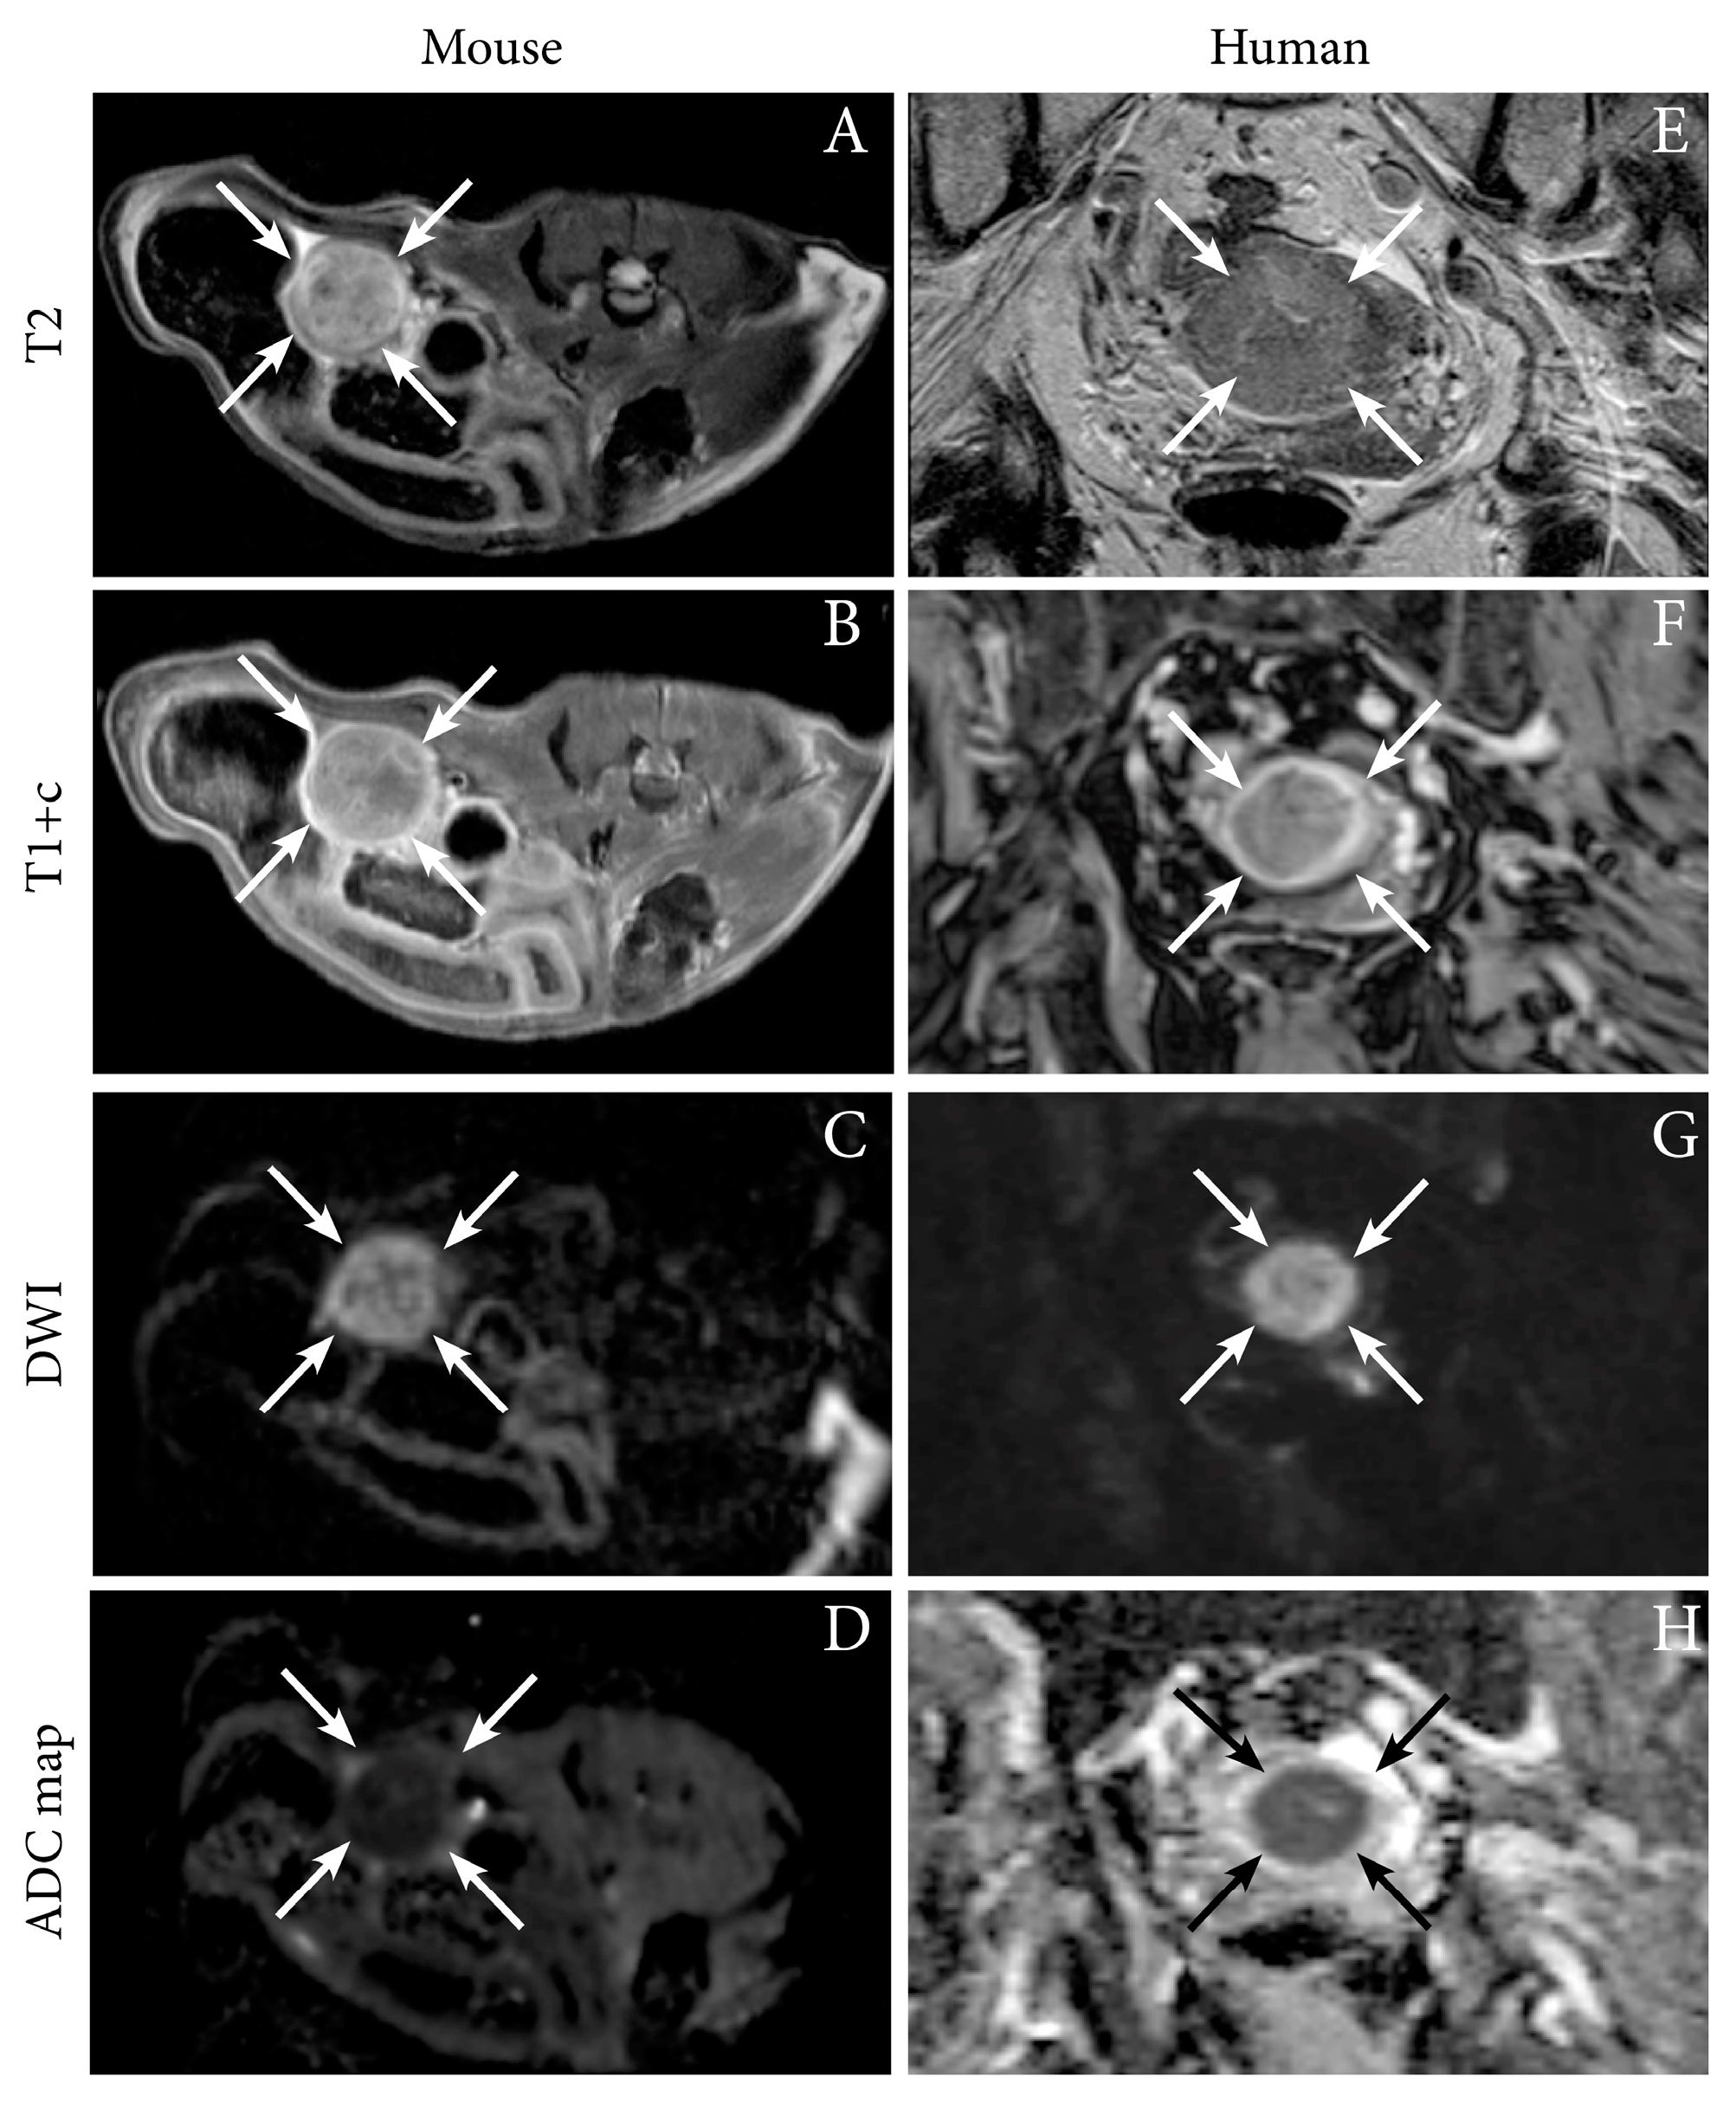

We have successfully imaged an orthotopic mouse model of EC using MRI, illustrating the feasibility of anatomical MR sequences (T1 and T2-weighted) to depict tumor growth in the uterine horns in mice [12]. Interestingly, the hyperintense tumor signal on T2-weighted series and the hypointensity of the tumor (relative to the surrounding myometrium) on contrast-enhanced (CE) T1-weighted series resemble that observed in human EC (Figure 1). Furthermore, the tumors in mice also exhibit restricted diffusion on DW-MRI with hyperintensity on high b-value images and corresponding low ADC value on the ADC map, being similar to that characteristically observed in humans (Figure 1, Table 1) [12]. For further insight into characteristic imaging findings at conventional imaging and novel promising imaging methods in human EC, we direct the readers to our recent review [16].

Figure 1. Axial magnetic resonance (MR) images depicting tumor (arrows) in an orthotopic endometrial cancer (EC) mouse model (Ishikawa cells) (AD), and corresponding axial MRI images visualizing a uterine tumor (arrows) in an 87-year-old woman with EC (grade 2 endometroid, FIGO stage IIIC1; same patient as in Figure 2) (E–H). (A,E) T2-weighted images depict hyperintense tumors and (B,F) T1-weighted contrast-enhanced images (T1+c) depict moderately enhancing uterine tumors. (C,G) Both the preclinical- and human tumors exhibit restricted diffusion with hyperintensity on high b-value diffusion-weighted imaging (DWI) and (D,H) corresponding hypointensity on the apparent diffusion coefficient (ADC) maps. Images A–D are reproduced under the open access CC BY license from a previous publication [12].